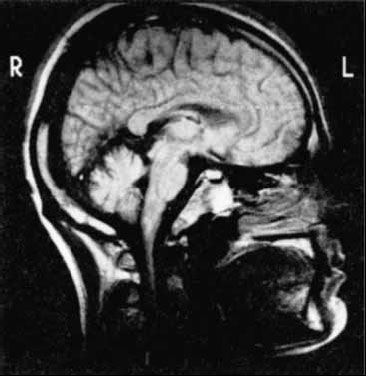

Рис. 2.17. Снимки мозга, полученные с помощью метода ядерно-магнитного резонанса (Carlson, 1992).

Поскольку водород содержится не в одинаковых концентрациях в разных тканях, что зависит как от структуры ткани, так и от ее метаболической активности, то при сканировании излучения этот факт используется для создания визуальной картины тканей. Получаемые с помощью указанного метода картины яснее и четче, чем изображения, представленные методом компьютерной томографии. Однако использование этого метода является более дорогим по сравнению с другими (рис. 2.17).